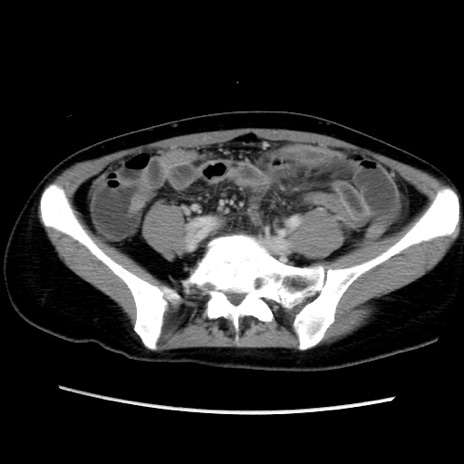

MRI(4日後)

【症例】40歳代女性

【主訴】上下腹部痛

【現病歴】2日目から下腹部痛あり。夜間は痛みで眠れなかった。昨日より上腹部痛と下痢が出現。臥位で痛みは軽快したため、休んでいた。本日になって臥位でも立位でも痛みが強くなってきたため救急要請。

【既往歴】子宮内膜症

【身体所見】部:平坦・軟、左上下腹部に圧痛あり、反跳痛あり。

【データ】WBC 21800、CRP 26.78